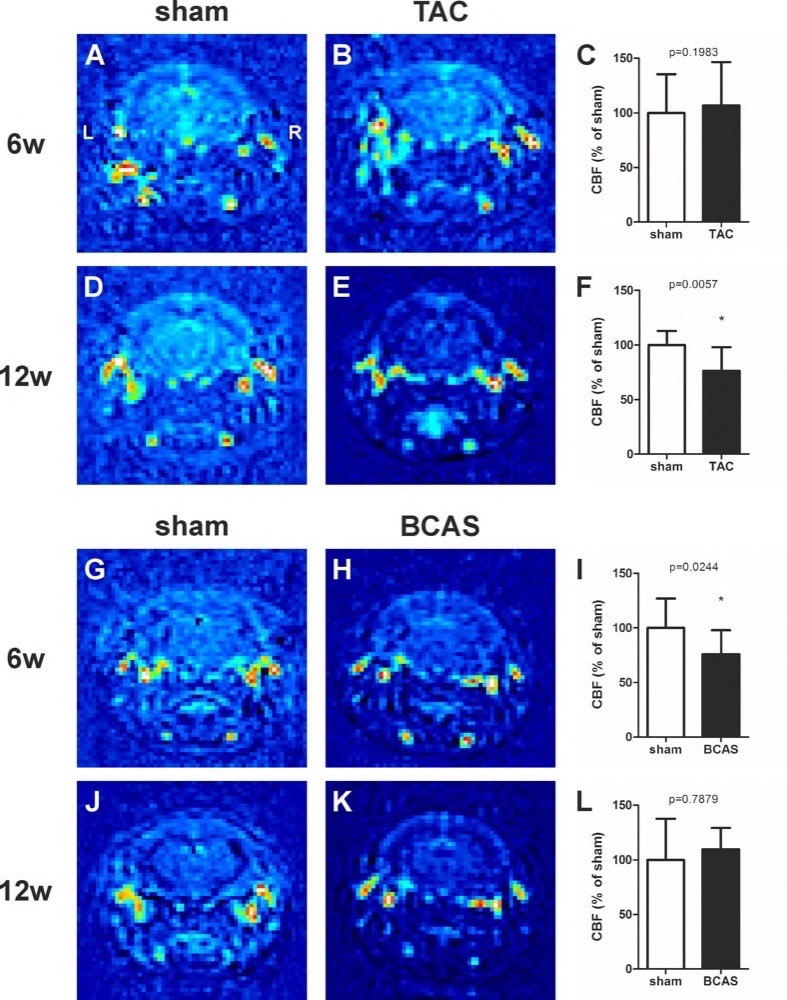

Chapter 6 Figure 3Representative MRI scans and graphs of CBF changes in TAC LDLr-/- mice at 6 weeks (6w) (A-C; n=11, 14) and 12 weeks (12w) (D-F; n=5, 12) and in BCAS C57Bl/6 at 6 weeks (G-I; n=9, 9) and 12 weeks after surgery (J-L; n=4, 7). The range of values from low (dark blue) to high (red) are relative to the background. * p<0.05 is considered significant.